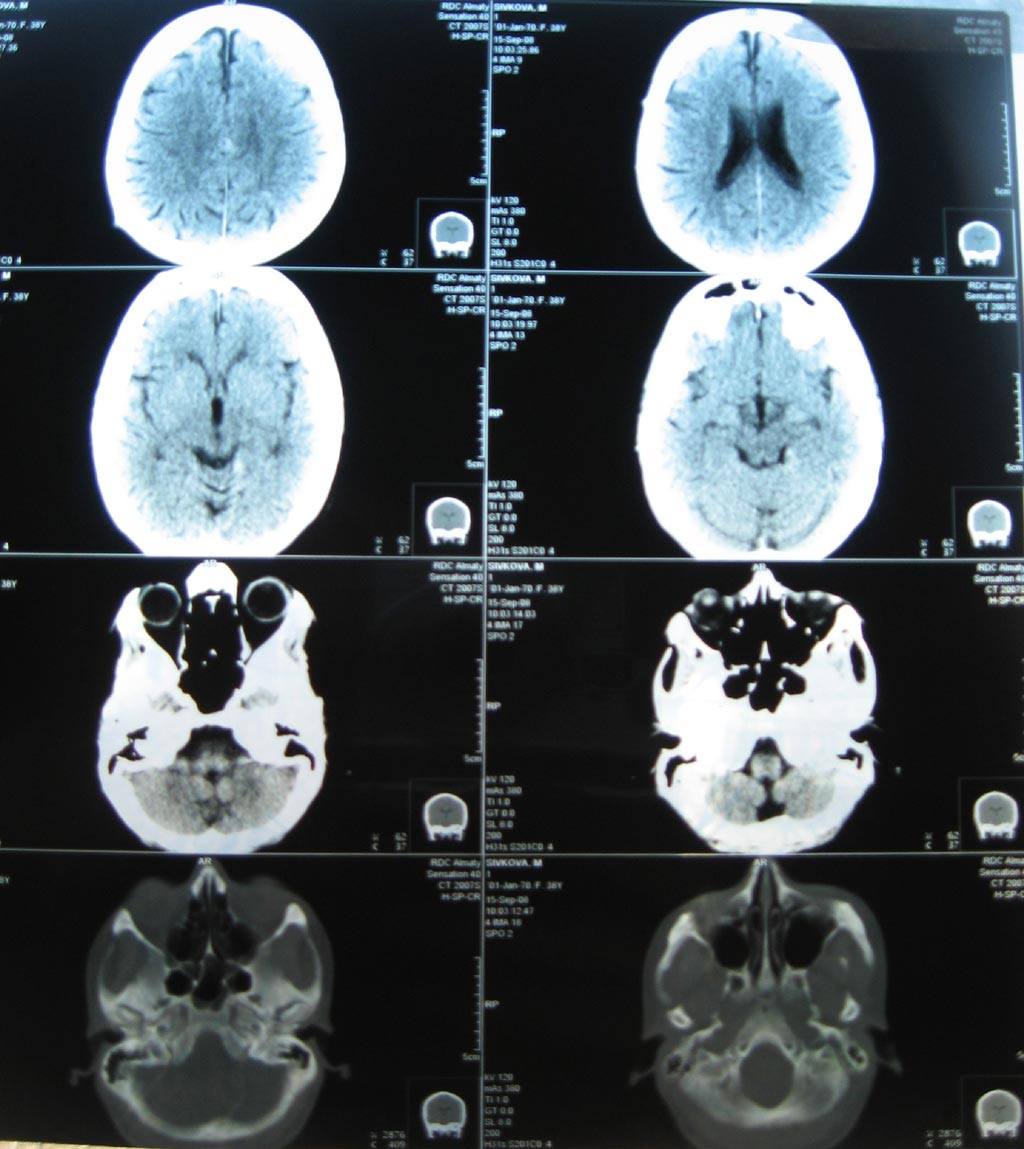

Токсическая энцефалопатия представляет собой рассеянное органическое поражение головного мозга, которое может развиться как после тяжелых острых отравлений нейротропными ядами, так и при хронических профессиональных нейроинтоксикациях.

Течению токсических энцефалопатии свойственны стойкость патологических проявлений, наличие остаточных явлений в отдаленном периоде и наклонность к прогрессированию вне контакта с токсическим агентом. Патологоанатомические данные указывают, что в основе токсических энцефалопатии лежат сосудистые поражения головного мозга и рассеянные дегенеративные изменения мозговой ткани.